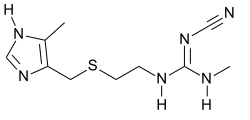

Несмотря на значительные усилия, длительное время не было найдено вещество, тормозящее кислотостимулирующее действие гистамина, и, только в 1972 году Джэймс Блэк, работавший в фирме «Smith Kline and French» (сегодня относится к фирме «GlaxoSmithKline»), Великобритания, испробовав более 700 разных структур, обнаружил, что соединение буримамид, содержащее имидазольное кольцо в боковой цепи, действует на рецепторы желудка (позже названые H2-рецепторами). За идентификацию H2-рецепторов и разработку лекарственных средств, блокирующих их, Блэк в 1988 году был удостоен Нобелевской премии[1].